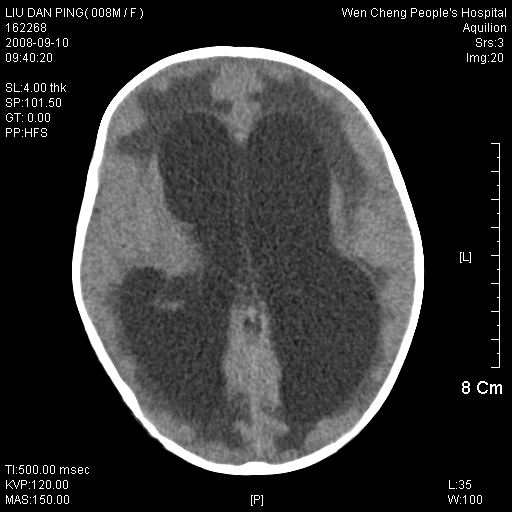

以下是引用卜一在2008-9-10 16:21:00的发言:[br]髓母细胞瘤伴梗阻性脑积水!支持![br]髓母细胞瘤特点:—般直径大于3.5cm,位于后颅凹中线之小脑蚓部。累及上蚓部的肿瘤延伸到小脑幕切迹之上,ct平扫肿瘤多呈均匀一致的高或等密度病灶,增强检查呈均匀一致的强化。病灶中有小坏死时,平扫亦可呈不均匀之混杂密度,注药后有增强。[br]

以下是引用zjzjr在2008-9-10 15:09:00的发言:[br]髓母细胞瘤伴梗阻性脑积水.